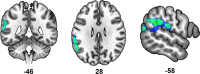

Age-related declines in sensorimotor performance have been linked to dedifferentiation of neural representations (i.e., more widespread activity during task performance in older versus younger adults). However, it remains unclear whether changes in neural representations across the adult lifespan are related between the motor and somatosensory systems, and whether alterations in these representations are associated with age declines in motor and somatosensory performance. To investigate these issues, we collected functional magnetic resonance imaging and behavioral data while participants aged 19-76 years performed a visuomotor tapping task or received vibrotactile stimulation. Despite one finding indicative of compensatory mechanisms with older age, we generally observed that 1) older age was associated with greater activity and stronger positive connectivity within sensorimotor and LOC regions during both visuomotor and vibrotactile tasks; 2) increased activation and stronger positive connectivity were associated with worse performance; and 3) age differences in connectivity in the motor system correlated with those in the somatosensory system. Notwithstanding the difficulty of disentangling the relationships between age, brain, and behavioral measures, these results provide novel evidence for neural dedifferentiation across the adult lifespan in both motor and somatosensory systems and suggest that dedifferentiation in these two systems is related.